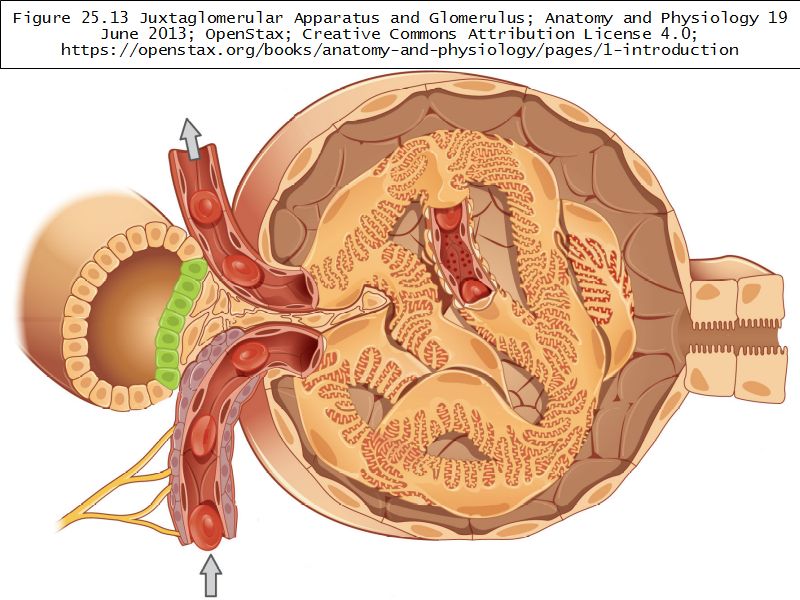

Juxtaglomerular complex

Area where distal convoluted tubule return to glomerulus and pass through the notch between the afferent and efferent arterioles. Modification of the wall of the tubule and afferent arteriole and presence of specialised cells in the connective tissue.